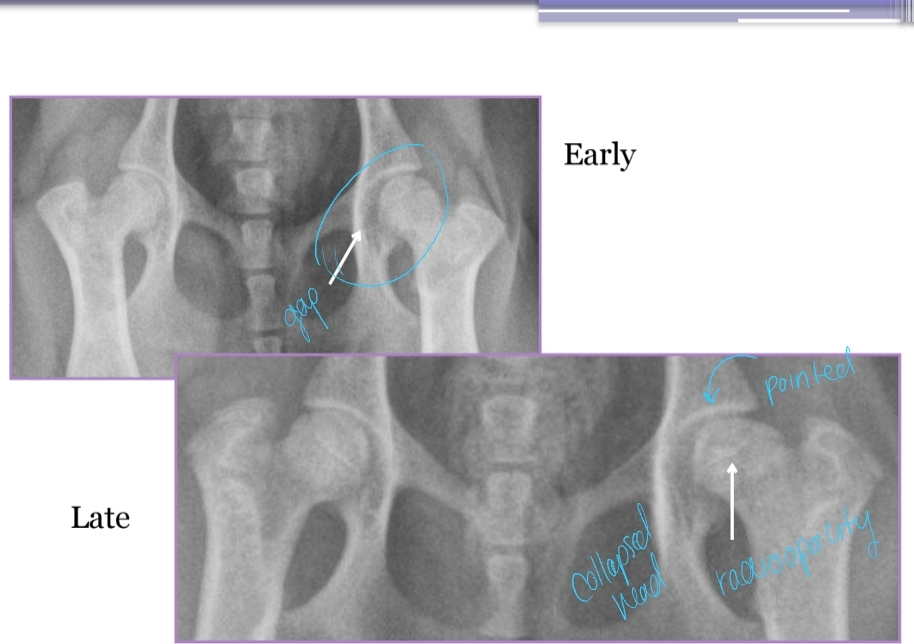

Diagnostic Imaging for Hip Dysplasia

VD most useful

Want >50% acetabular coverage!

Rads: Bone shape, remodeling, osteophytosis(neck), enthesiophytosis (Morgan’s line), laxity

Do not treat the radiograph!

Dt: signalment & Radiographs

Early: Increased opacity of lateral epiphysis (femoral head) and joint space due to effusion

Late: Collapse/flattening/thickening of femoral head + neck, ± Femoral neck fracture